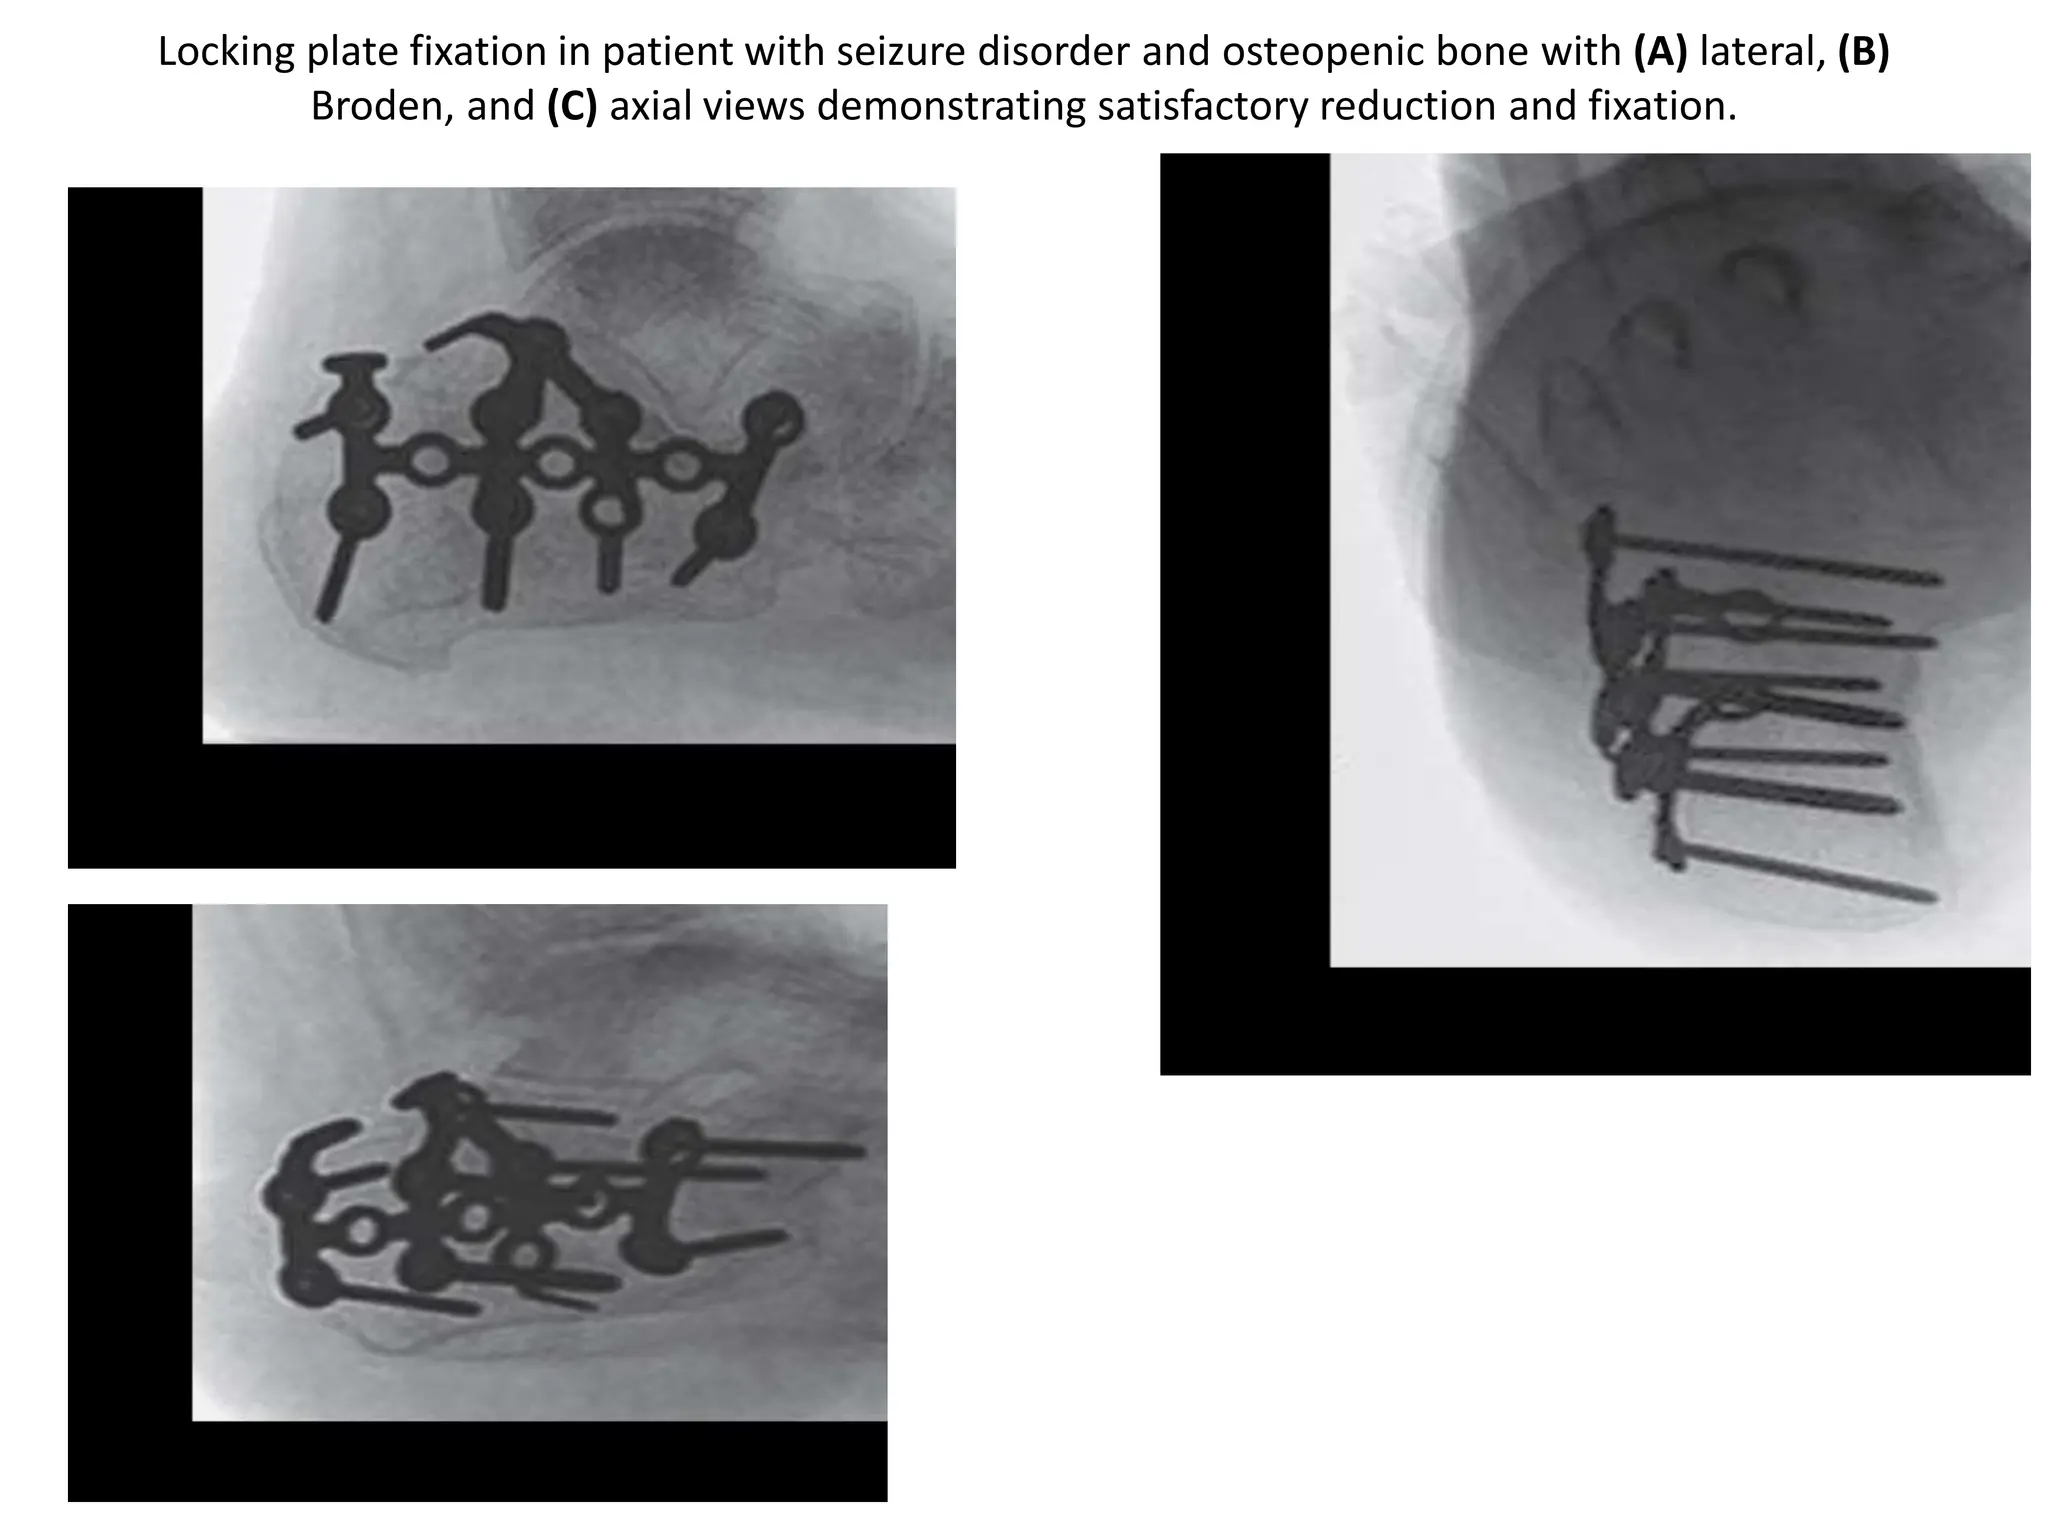

Locking plate fixation in patient with seizure disorder and osteopenic bone with (A) lateral, (B)

Broden, and (C) axial views demonstrating satisfactory reduction and fixation.

Locking plate fixationin patient with seizure disorder and osteopenic bone with (A) lateral, (B) Broden, and (C) axial views demonstrating satisfactory reduction and fixation.